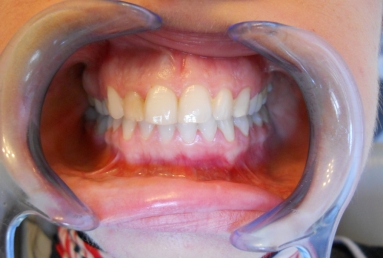

Initial clinical situation: upper lateral incisor with a big composite filling and an old root canal treatment. that caused in time a grey discoloration of the tooth. Internal tooth whitening would not give a good result in this case, because of the composite filling, and also because the whitening is not stable in time. This is why the decision was to restore the tooth with a very esthetic full ceramic crown, which does not change colour in time, at the same time protetcting a non vital tooth against fracture.